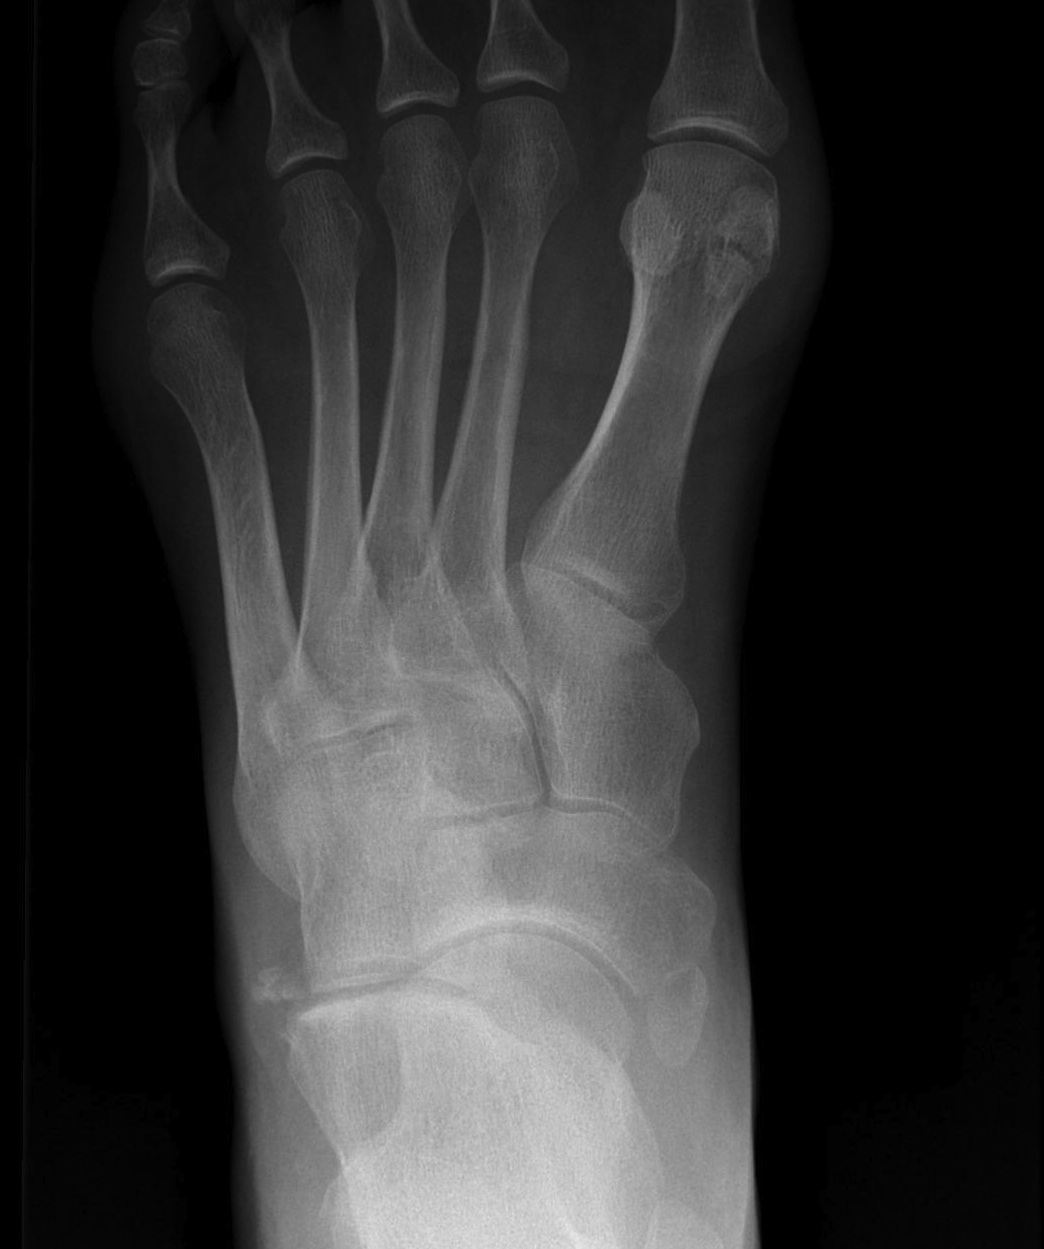

Classification

| Type I | Type II | Type III |

|---|---|---|

|

Small ossicle proximal to insertion In the Tibialis posterior tendon |

Triangular ossicle Connected to navicular via syndesmosis May fracture with injury |

Enlarged medial navicular Cornuate navicular Likely that Type II accessory navicular has fused |